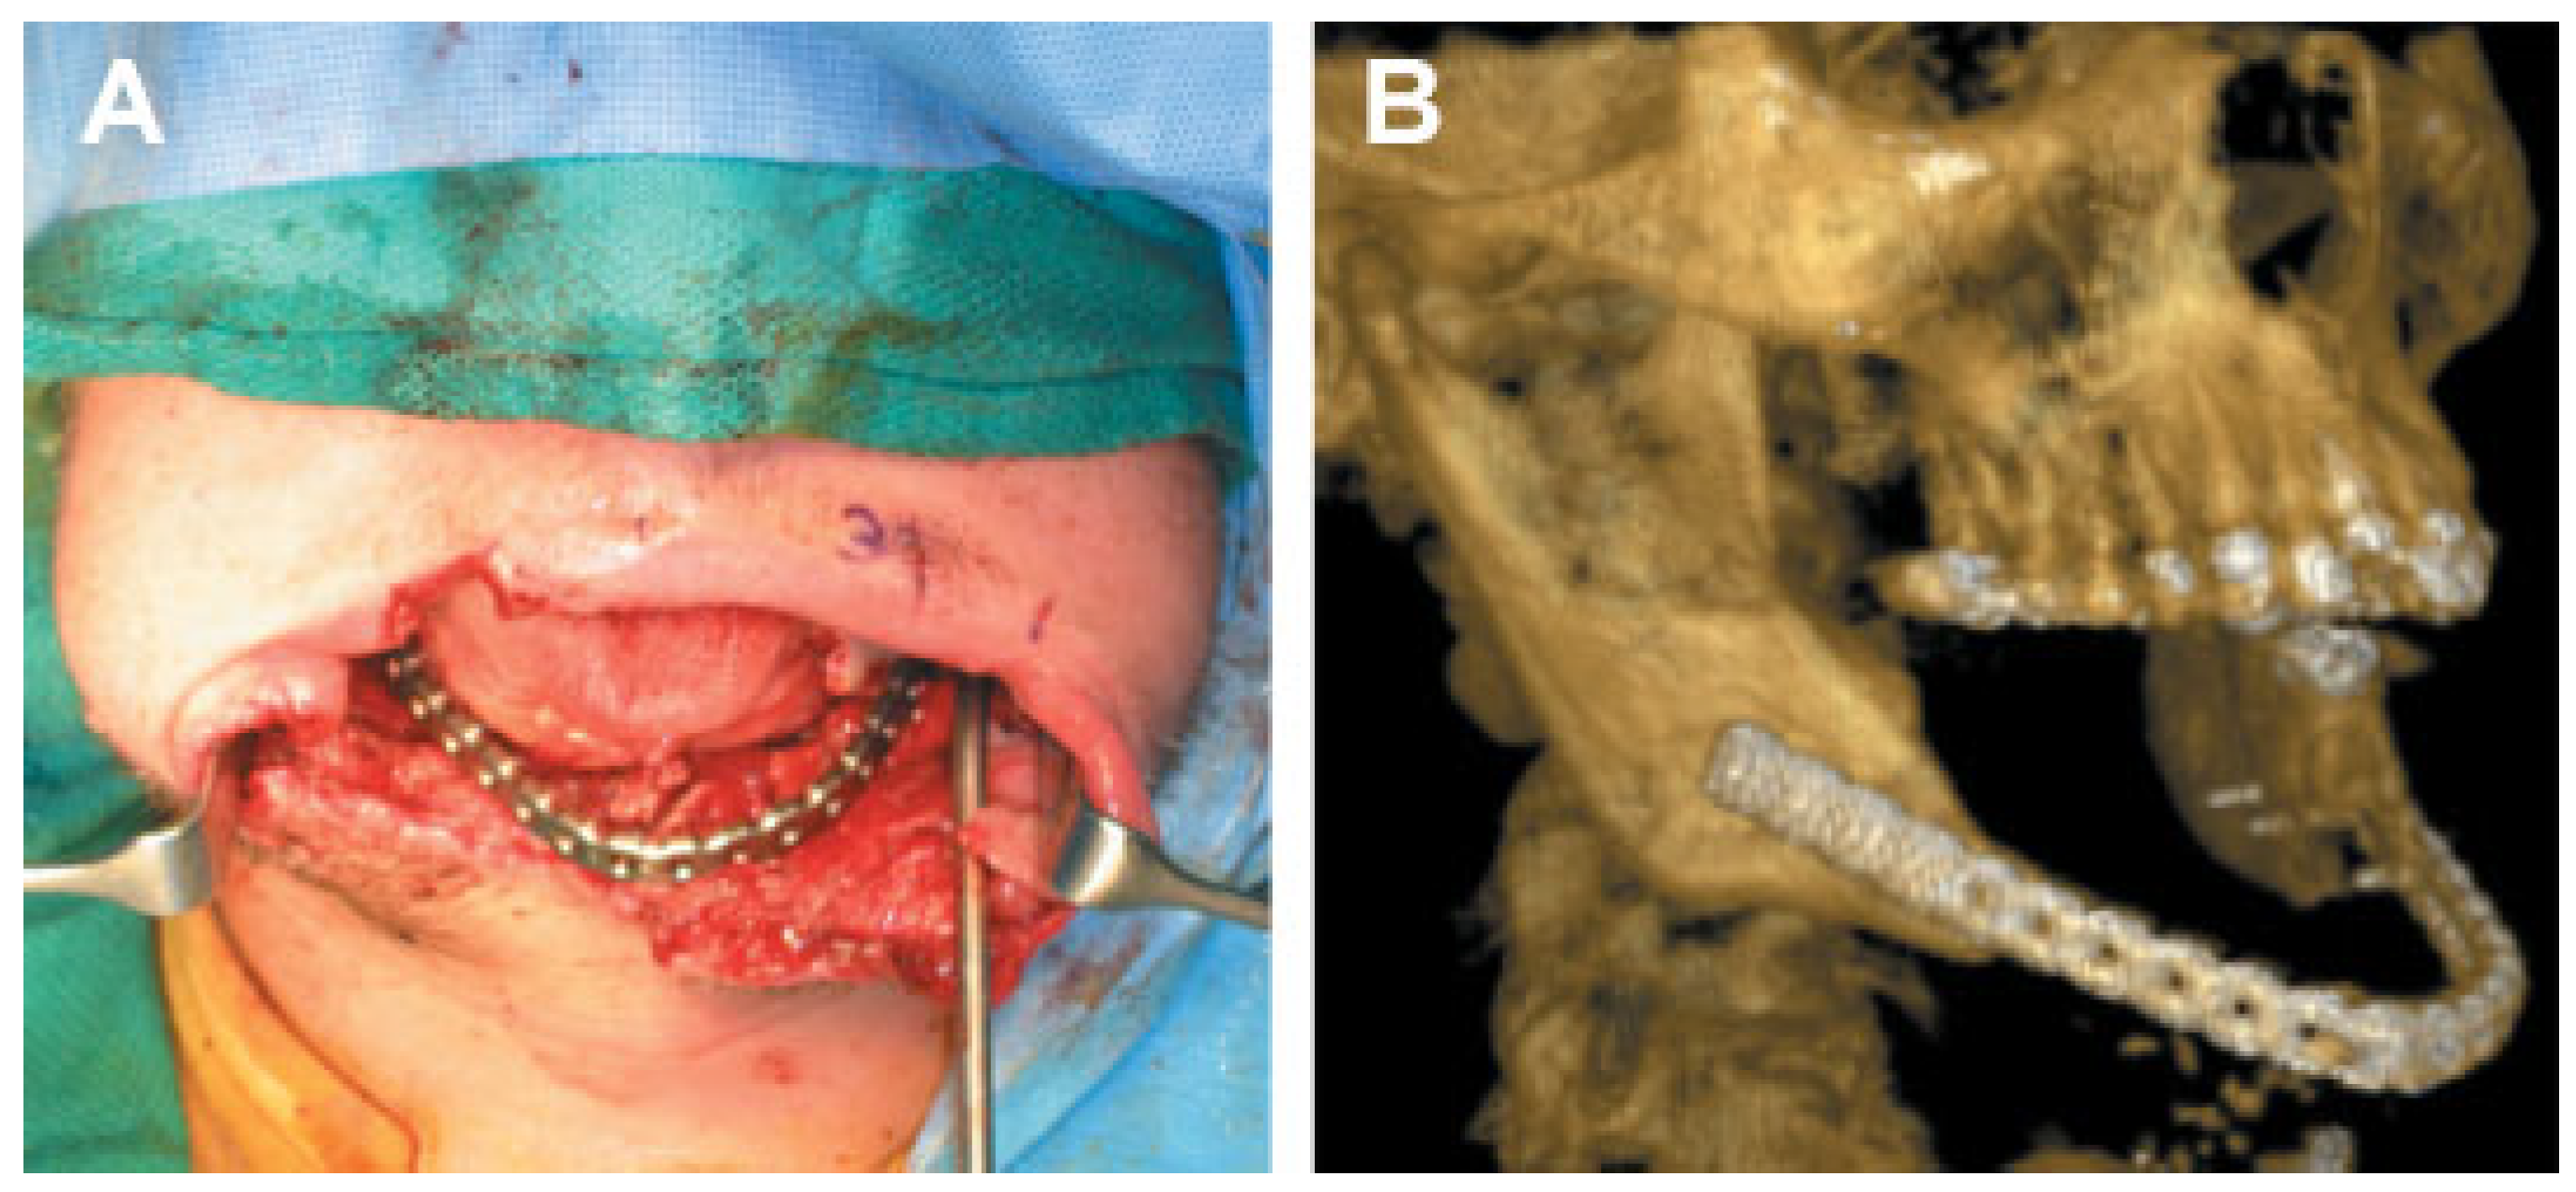

Patient 2 arrived at BAMC 1 week after injury in stable condition. He was taken to the operating room for examination under anesthesia and debridement of his wounds. The Le Fort II fracture was anatomically reduced and fixated with miniplates. Postoperatively, computed tomography (CT) scans were performed to fabricate a mandibular stereolithography resin model. Based on the resin models, reconstruction plates were bent preoperatively.

Patient 2 returned to the operating room 2.5 weeks post- injury for open reduction internal fixation of the mandibular fractures through a neck incision. The comminuted right ramus and condyle fractures were deemed nonrepairable. After debridement of the comminuted fractures, the right ramus and condyle area was reconstructed with an immediate costochondral graft and a 2.4-mm reconstruction plate.

The comminuted left condyle and body fractures were re- paired with 2.0-mm reconstruction plates (Figure 5). A right cheek wound was closed in layers after debridement and placement of a drain.

Figure 5.

(A,B) Primary fracture reconstruction; comminuted right condyle debridement and reconstructed with immediate costochondral graft. (Images are courtesy of Colonel Robert Hale.).